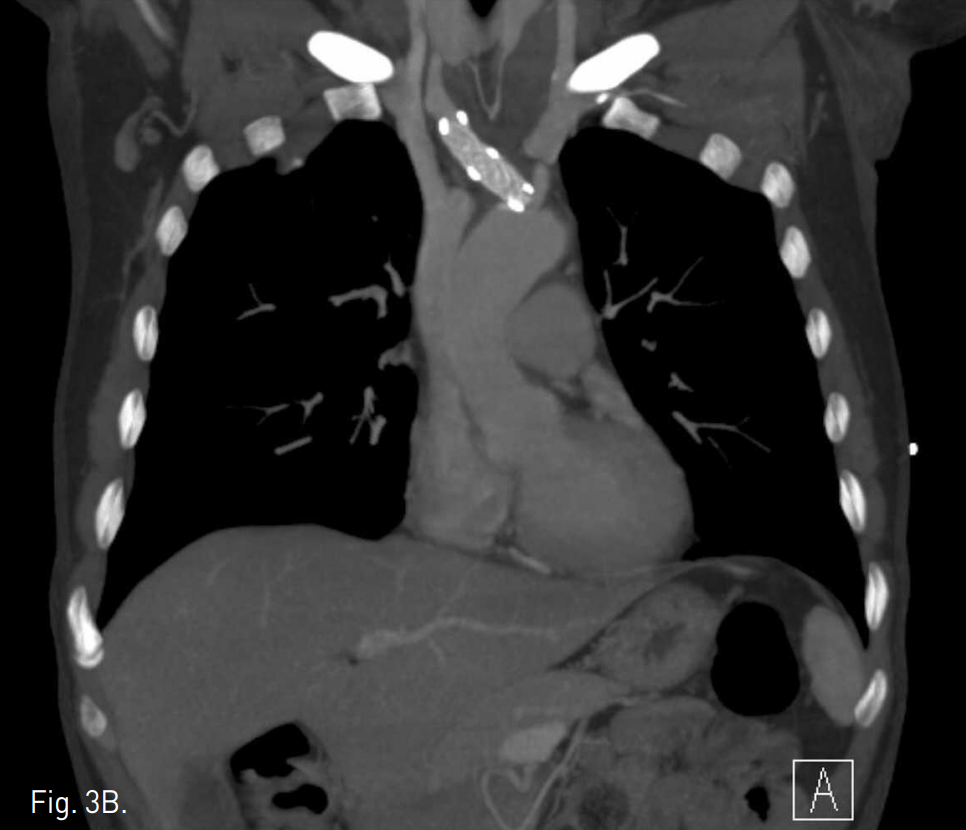

Fig. 3

A, B. On axial (A) and coronal MIP (B) images of follow up CT scan 2 weeks later, thelesion of right brachiocephalic trunk has been completely excluded. Both common carotid and right subclavian arteries are normally visualized.

흉부 CT에서 aortic arch에서 약 0.5cm 떨어진 right brachiocephalic trunk에 약 2.7cm 길이의 dissection이 관찰되며 약 1.6cm의 pseudoa neurysm이 동반되어 있다. 또한 주위 종격동에 혈종이 있다(Fig. 1A, B). Supine position에서 시행한 복부대동맥조영술에서도 right brachiocephalic trunk의 dissection과 pseudoaneurysm이 잘 관찰된다(Fig.2A). Wire와 catheter를 이용하여 병변 부위를 통과한 후, covered stent를 설치하였다(Fig. 2B). 2주 후 시행한 추적 흉부 CT상 dissection과 pseudoa neurysm은 더 이상 보이지 않았다(Fig. 3A, B).

2주 후 시행한 흉부 CT에서 stent는 잘 위치하고 있으며, right brachiocephalic trunk에 있던 dissection과 pseudoaneurysm은 호전되었다.